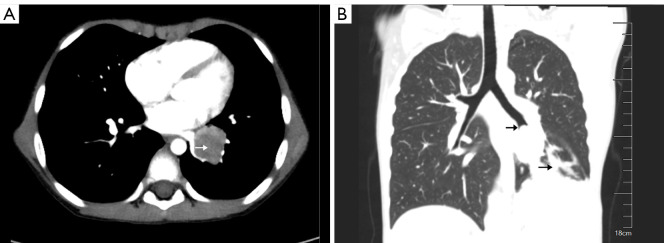

Pediatric pulmonary mucoepidermoid carcinoma in a 5-year-old patient.

1例5岁儿童肺黏液表皮样癌。